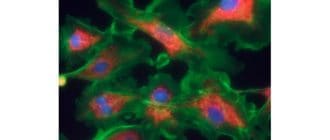

毛状細胞白血病は、血液癌の一種である。このタイプの癌は、骨髄などの血液を形成する組織、または免疫系の細胞で始まります。 毛状細胞白血病は、すべての白血病の約2%を占め、女性よりも男性においてより一般的であり、高齢者におい […]

線維肉腫は線維芽細胞として知られている細胞に影響を及ぼすまれな種類の癌です。線維芽細胞は、体全体に見られる線維性組織の形成を担う。筋肉を骨に結びつける筋肉は、繊維組織でできています。 線維肉腫が発症すると、体の線維芽細胞 […]

造血幹細胞移植は、いくつかのタイプの癌の治療として最初に使用されたが、現在では様々な自己免疫疾患の治療として広く使用されている。 しかし、米国食品医薬品局(FDA)は、がんに使用する造血幹細胞移植(HSCT)を承認してい […]